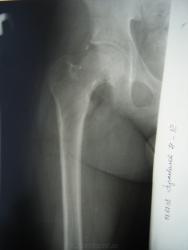

Юношеский эпифизеолиз головки левого бедра

В чем, по Вашему, в данном случае состоят признаки эпифизеолиза - в чуть большей ширине зоны роста?...ведь существенного нарушения конгруэнтности нет....или есть еще что то? Если Вас не затьруднит, прокоментируйте.

Может действительно снимок не совсем информативный, мне кажется на МРТ лучше видно.

Теперь понятно, все таки основной признак - расширение зоны роста, а как вторая сторона, она попала в зону интереса или работали на МРТ только с одной конечностью?